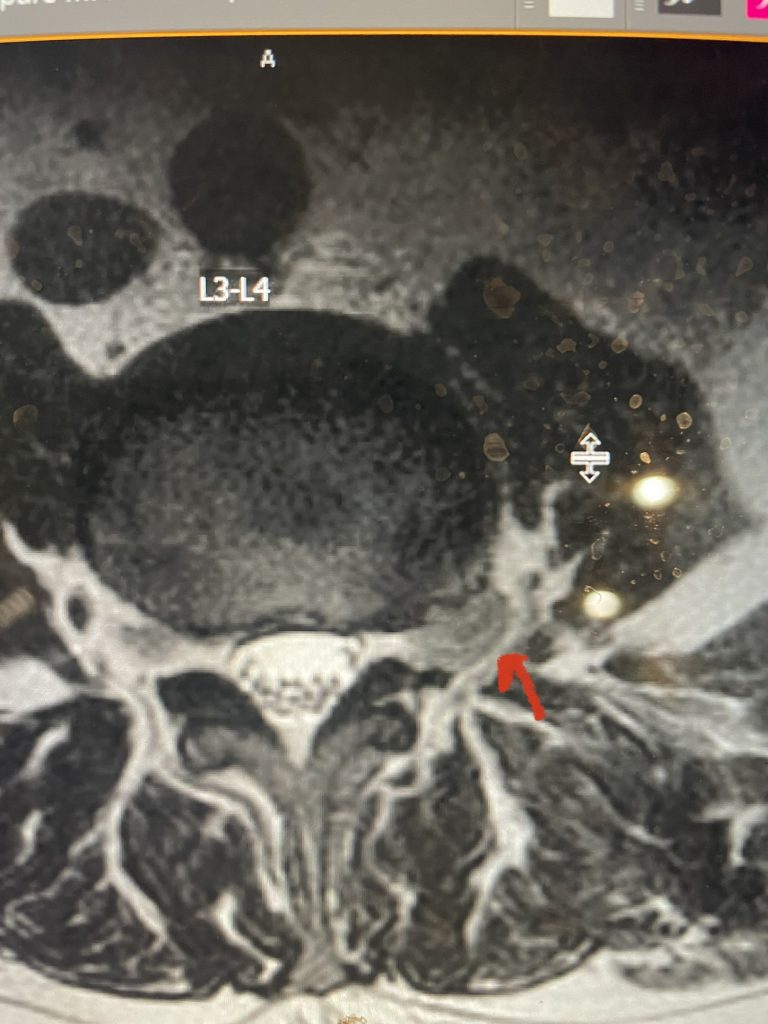

Fig 7: Sagittal T2-weighted lumbar MRI with side by side comparison of the normal open right L3-4 foramen (red arrow) compared to the left L3-4 foramen filled with a large disc fragment (red arrow).

Here is a case of an extraforaminal disc fragment causing severe pain and weakness: This 60-year-old male presented with severe anterior thigh pain, numbness, and weakness for 3 weeks. He had failed epidural steroid injections. His left leg buckled when he walked. Imaging revealed a massive left L3-4 extraforaminal disc herniation, beyond the facet (Fig 6). This was severely compressing the left L3 nerve root in the L3-4 foramen (Fig 7). It was felt that the patient required surgery, as he would not be able to participate in physical therapy and had a neurological deficit. We performed an extraforaminal approach and removed a massive disc fragment that was revealed as the intertransverse membrane was reflected from the L4 transverse process-facet junction. We were able to visualize the L3 spinal root exiting above that had been compressed by the large fragment we removed (Fig 8). The patient post-op had a dramatic improvement neurologically and with significantly improved pain in his leg.